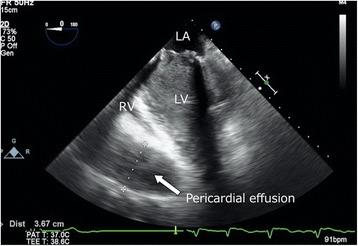

Acute bioprosthetic valve thrombosis can occur after surgery and sometimes cause hemodynamic instability and cardiogenic shock. Risk factors for bioprosthetic valve thrombosis are hypercoagulability, atrial fibrillation, atrial dilatation, low cardiac function, and lack of anticoagulation therapy. The authors present a case of severe mitral stenosis due to bioprosthetic valve thrombus. The patient was diagnosed with dilated-phase hypertrophic cardiomyopathy and underwent mitral valve replacement. He required venoarterial extracorporeal membrane oxygenation (VA-ECMO) due to extremely low cardiac output and was scheduled for left ventricular assist device (LVAD) implantation. Transesophageal echocardiographic examination before LVAD implantation revealed severe mitral stenosis due to bioprosthetic mitral valve thrombus, which was not detected by transthoracic echocardiography in the intensive care unit and contributed to the low cardiac function. The thrombus was removed through an unscheduled left atriotomy before LVAD implantation. The possibility of bioprosthetic valve thrombosis must be considered when the patient is dependent on VA-ECMO support. Early transesophageal echocardiographic examination of the bioprosthetic valve may be helpful and contribute to surgical decision-making.

急性生物瓣血栓形成可在手术后发生,有时会导致血流动力学不稳定和心源性休克。生物瓣血栓形成的危险因素包括高凝状态、心房颤动、心房扩大、心功能低下以及缺乏抗凝治疗。作者报告了一例因生物瓣血栓导致严重二尖瓣狭窄的病例。该患者被诊断为扩张型肥厚性心肌病并接受了二尖瓣置换术。由于心输出量极低,他需要静脉-动脉体外膜肺氧合(VA-ECMO)支持,并计划植入左心室辅助装置(LVAD)。在植入LVAD之前进行的经食管超声心动图检查显示,由于生物瓣二尖瓣血栓形成导致严重二尖瓣狭窄,而重症监护病房的经胸超声心动图未检测到该血栓,这也是心功能低下的原因。在植入LVAD之前,通过意外的左心房切开术清除了血栓。当患者依赖VA-ECMO支持时,必须考虑生物瓣血栓形成的可能性。早期对生物瓣进行经食管超声心动图检查可能会有所帮助,并有助于手术决策。